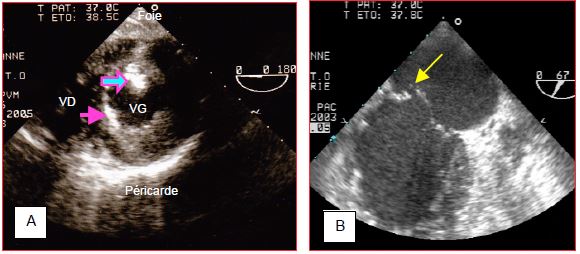

Figure 9.19: Altérations de la contractilité segmentaire à l'ETO: deux cas différents d'occlusion de l'IVA. A (systole) et B (diastole): vues 4-cavités 0°; le VG est dilaté, le septum (S) et la paroi latérale (PL) ont une activité contractile (flèches rouges) alors que toute la partie antéro-apicale (flèches jaunes) est immobile, amincie et arrondie (akinésie). C (systole) et D (diastole): vues 2-cavités 90° d'un autre patient; la paroi inférieure (PI) et la paroi antérieure basale (PA) se contractent et s'épaississent (flèche rouge) en systole, mais la zone antéro-apicale (flèche jaune) reste immobile entre la systole et la diastole (akinésie). La flèche verte indique une zone anévrysmale (dyskinésie). Dans le premier cas, la paroi akinétique est très mince et probablement déshabitée; la récupération après revascularisation est illusoire. Dans le deuxième cas, la paroi akinétique présente une épaisseur et une structure échographique normales, qui laissent supposer une bonne viabilité après revascularisation.